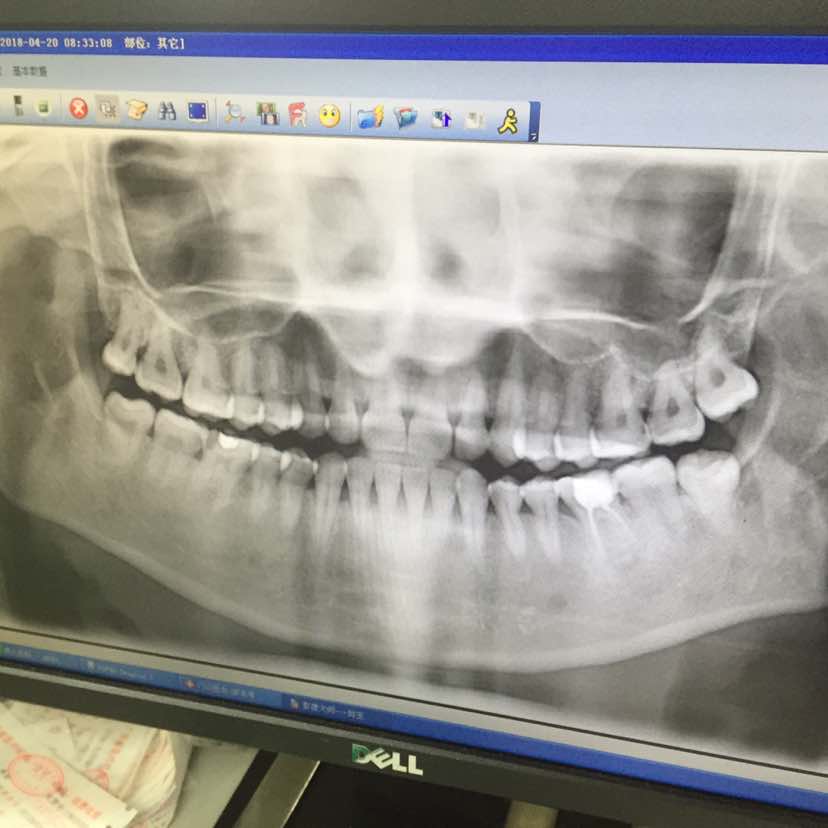

左下牙的一颗智齿引起了牙龈肿痛,由过年前一直反反复复到现在,牙齿没痛,就是智齿周的牙龈痛,在三个星期前复查指标一切稳定,问了梁教授能不能拔智齿,她说可以,当天挂不到口腔科的号,就挂了第二天早上的号,去看了拍了片,然后一不小心那天上午🈷经来了,跟我说不能拔,要经期过10天才能拔牙!

又回家慢慢等待,终于今天是时候了,取号排队等叫名,然后到了我的时候,我告诉医生是红斑狼疮患者,医生说要教授签个可以拔牙的证明,我一下懵了,以为今天又拔不了了,幸好今天梁教授有出门诊,然后屁颠屁颠地跑去三楼麻烦教授帮我签个字,然后回七楼交费等待拔牙,说要拔掉两颗,拔一颗的话没有咬合,另一颗会长长,最后决定了拔掉两颗,先给上麻醉药,我不敢睁眼,只听见医生说我这牙好大不好拔,然后叫助手拿把剪刀,就开始了,先剪然后用小锤子敲再拔,妈呀~我感觉我觉得动静好大,半个钟过后两颗智齿都拔出来了。医生叮嘱完注意事项就坐地铁回家了,到家的时候麻药效也过了,开始痛得我站也不是,坐也不是,躺也不是~最后吃了止痛跟消炎的药💊,希望过两天会好,不再痛了,被这两颗智齿折腾的够呛的,希望后面好好的,狼🐺友们如果弄牙齿一定要告诉牙医自己是狼的情况,因为我们凝血功能不好,也有的血小板低,说清楚情况医生也会小心点,最后是两张牙龈的图片